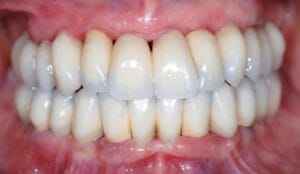

Examples of our work

Navigated implants represent a breakthrough in dental implant precision, using advanced 3D-guided technology to ensure optimal placement and alignment. At Wimpole Street Dental Clinic, our navigated implant case studies highlight how we leverage this technology to provide predictable, accurate, and minimally invasive solutions for tooth replacement. Each case reflects our dedication to innovation and patient-focused care, resulting in natural-looking, secure implants that restore both function and confidence.